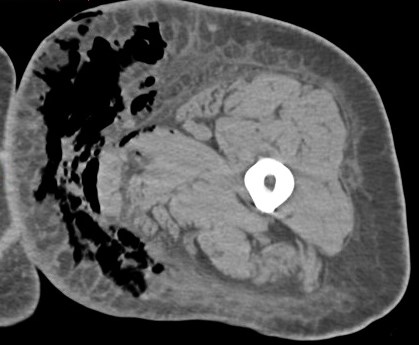

Figure 3 for case Necrotizing fasciitis ( RID3447 )

Figure 3